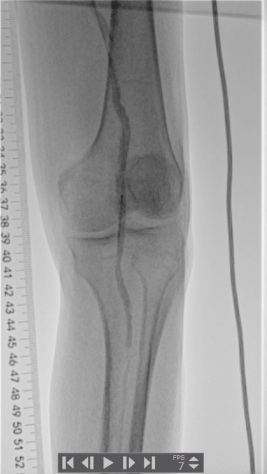

1.穿刺右侧股总动脉,“翻山”至对侧股总动脉,造影:股浅、股深动脉、腘动脉完全闭塞,膝下可见少量侧支动脉代偿。

▲患者术中即时造影显示股浅、股深动脉完全栓塞

▲腘动脉可见充盈缺损

▲膝下主干动脉未见显影